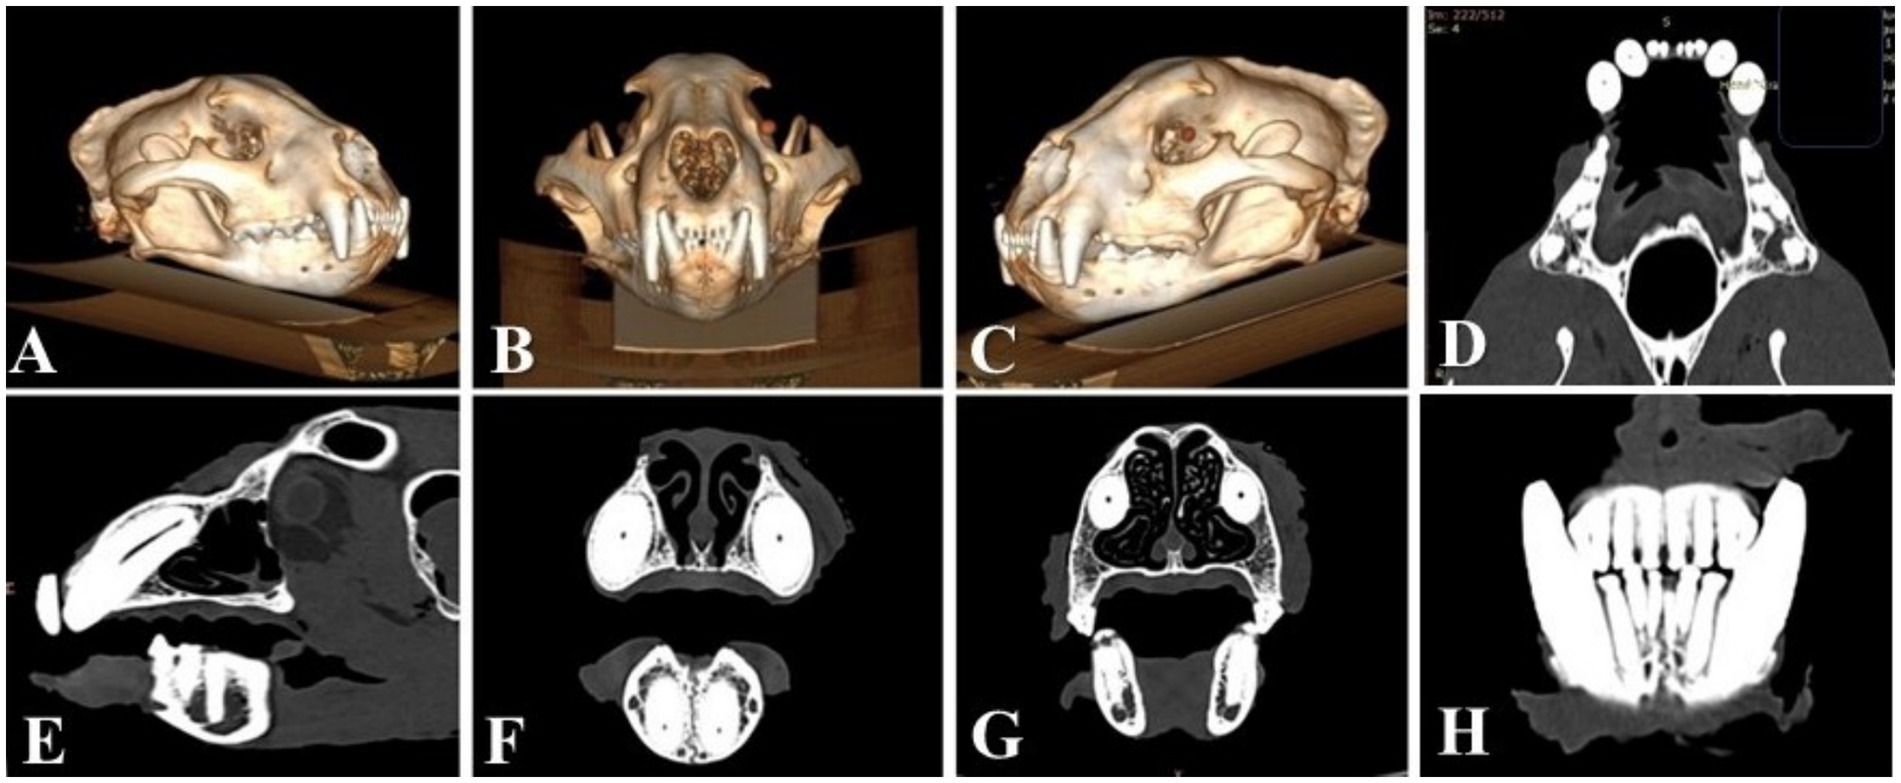

Wild animals in captivity are prone to developing dental diseases. Pink discoloured canine teeth in jaguars are often seen in wildlife photographs but are rarely reported in the literature, and none have been formally investigated. Within 24 hours post-mortem, the oral cavity of a zoo jaguar was investigated using computed tomography (CT). One pink discoloured canine tooth was atraumatically extracted, fixed and stained for histological and transmission electron microscopic (TEM) examination. The intravitam pink discoloured canine tooth had no periodontal or periapical lesions, and microscopically the dental pulp presented numerous ectatic blood vessels with numerous thrombi that occluded the blood vessels. A high percentage of thrombi presented the retunneling phenomenon. Fluorescence imaging confirmed the presence of haemoglobin in the dentinal tubules. The study, the first of its type, sheds light on an intravitam pink discoloured canine tooth opening, a hitherto unexplored topic in zoo dentistry. For the skull to be accepted into the zoological collection of the National Institute of Biology, the extracted canine tooth had to be replaced by a 1:1 scale prosthodontic reconstruction, macroscopically identical to the natural tooth. Prosthodontic reconstruction was performed using computer-aided design and manufacturing (CAD/CAM) technology. The study, the first of its type, investigates an intravitam pink discoloured canine tooth in a jaguar, a hitherto unexplored topic in zoo dentistry, and describes its prosthodontic reconstruction.